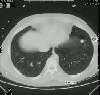

The patient had a CT performed that demonstrated the paratracheal mass to be densely calcified (a finding not readily appreciable on the plain film). The calcified mass extended in to pretracheal region. The superior vena cava is displaced but there is no mediasitnal fibrotic reaction evident to suggest fibrosing mediastinitis. The calcified nodule was also again identified. (Click on small image to view larger radiograph)